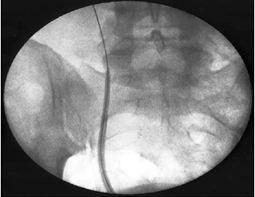

This is a retrospective study analyzing 81 patients who benefited from PCNL (n=45) and URS (n=36) for lower calico stones between July 2012 and June 2015 in the urology department of the Mohamed V military hospital in rabat. The general characteristics of the patients were comparable in the two groups (Age, Gender, BMI). The mode of revelation was often nephretic colic in the PCNL group than in the URS group, in a small number the stone was discovered incidentally. Clinical success was defined by stone-free status or the presence of an asymptomatic residual fragment less than 3 mm. The chi2 test is used to compare the success rate, postoperative complications and transfusion rate, the t test and the witney test were used to compare the quantitative variables. The results are defined as significant for a p<0.05, the statistical analysis is performed using the SPSS software. The majority of patients had a double J catheter 3 to 4 weeks before the URS for passive dilation of the ureter. In the lithotomy position, cetherization of the ureter by a ureteral probe, a safety guide is left in place, an access sheath (45cm for women and 55cm for men) is slipped over the guide under fluoroscopic control (Figure 1).

The Wolf 8 ureteroscope (Figure 2), is introduced through the sheath. The fragmentation of the calculus is carried out with the fiber 260 of 0.2mm in diameter (Figure 3), then extraction of the calculi using the N gage pliers (Figure 4). A double J probe is left in place for 31 patients, the radiographic control is carried out by an unprepared abdomen or a CT scan 4 weeks after the operation. Patients who underwent PCNL were placed in a modified lateral position (Figure 5). The lower caliciel group was under fibroscopic control and the introduction of the hydrophilic guide using the Amplatz Ch 26 sheath for all patients. The procedure is performed using the Wolf CH24 Nephroscope (Figure 6). Fragmentation of the stones using a combination of pneumatic and ultrasonic energy, then extraction of the stones with biopsy forceps. A Ch 18 Fr nephrostomy is left in place for 48 to 72 hours, the ureteral catheter and the bladder catheter withdrawn in the following days. An X-ray check is performed on an unprepared abdomen 4 weeks after the operation.